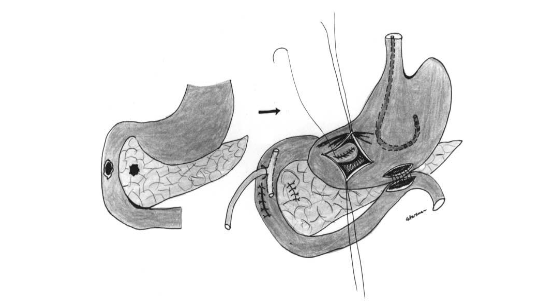

Phân loại AAST – I, II (Lucas I)

A – Thương tổn tụy độ II

B – Dẫn lưu HCMN, mở thông túi mật, mở thông dạ dày, mở thông hỗng tràng

A – Thương tổn độ I ở đầu tụy, độ III (AAST) ở D2

B – Khâu vết thương tá tràng D2, mở thông túi mật, mở thông dạ dày, mở thông hỗng tràng, dẫn lưu HCMN và cạnh tá tràng (theo C.Arvieux, C.Létoublon 2005)